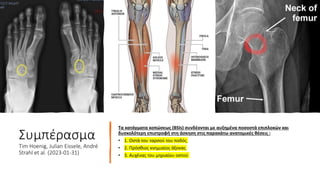

Τα κατάγματα κοπώσεως (BSIs) συνδέονται με αυξημένα ποσοστά επιπλοκών και

δυσκολότερη επιστροφή στη άσκηση στις παρακάτω ανατομικές θέσεις :

• 1. Οστά του ταρσού του ποδός

• 2. Πρόσθιος κνημιαίος άξονας

• 3. Αυχένας του μηριαίου οστού